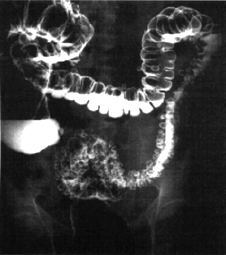

6.7.1 Diverticoli

del colon

La seguente radiografia a contrasto

mostra un esempio.